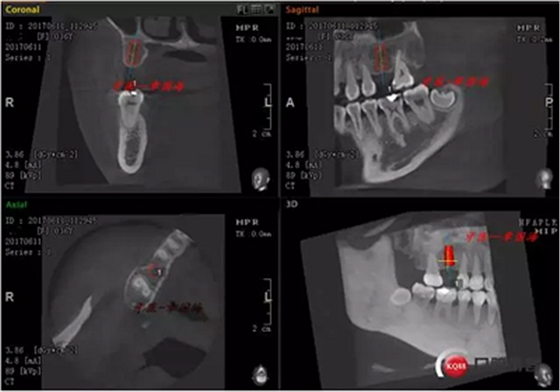

1.右上6缺失,種植修復(fù)。因空間關(guān)系選擇相應(yīng)植體,ItI(士卓曼)4.1X10mm SP SLA.

CT如圖示